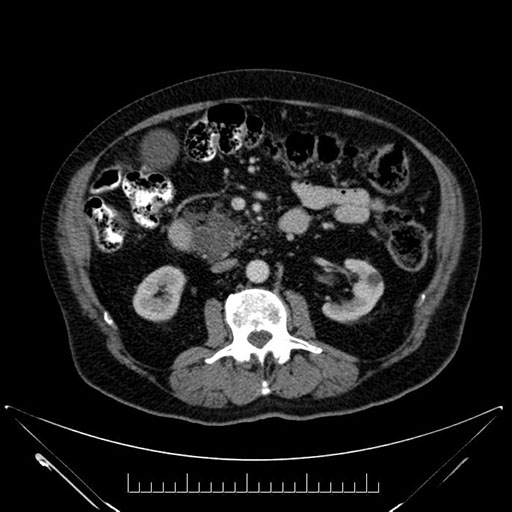

Imaging Analysis

Look through the patient's CT scan to identify any areas of concern for the necessary procedure.

Based on your CT findings, which issue(s) would give reason for "planned slowing down moment(s)" in this case?